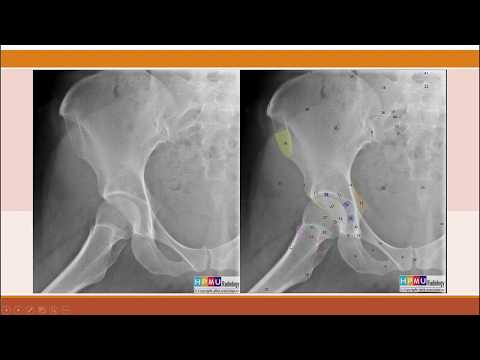

Jun 4, 2022Giải phẫu X quang chi dưới 1. Mào chậu; 2. Hố chỏm đùi; 3. Gai chậu trước dưới; 4. Thân xương mu; 5. Ngành dưới xương mu; 6. Khớp cùng chậu; 7. Lỗ bịt; 8. Ụ ngồi; 9. Ngành xương ngồi; 11. G

Cấu trúc giải phẫu học vùng cổ chân. Ba xương tạo nên khớp cổ chân gồm: Xương chày: một trong hai xương cẳng chân, chịu sức chính ở cẳng chân. Xương mác: là xương cẳng chân thứ hai. Và xương sên: một